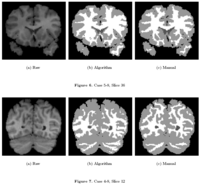

Multiscale Shape Segmentation TechniquesTo represent multiscale variations in a shape population in order to drive the segmentation of deep brain structures, such as the caudate nucleus or the hippocampus. More... | |